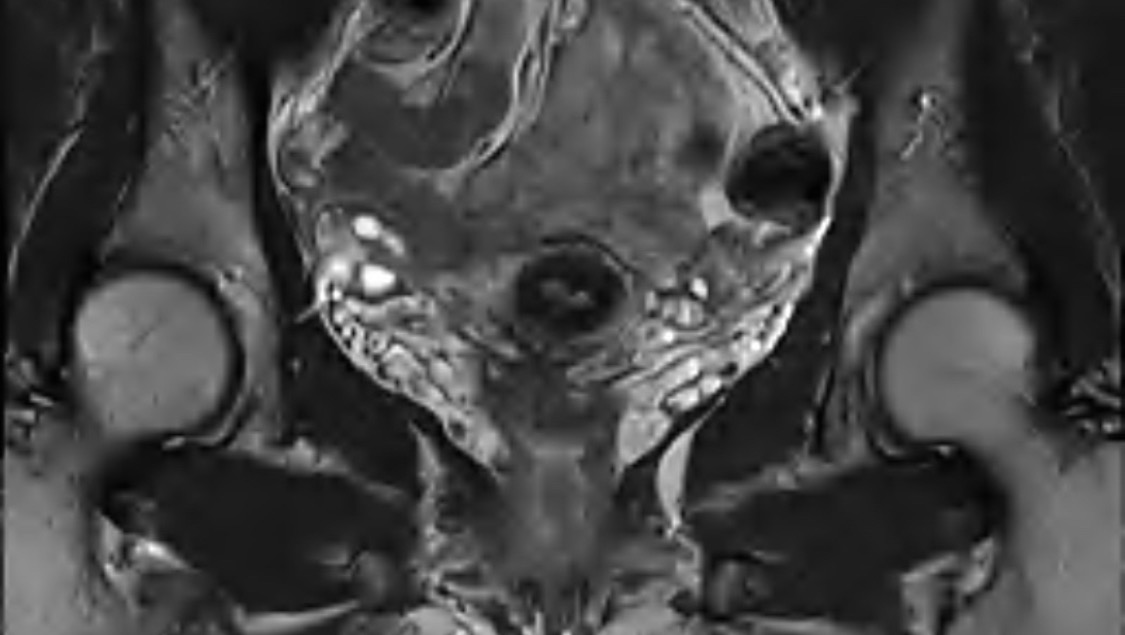

After years of unexplained pain, I finally have an answer — deep infiltrating endometriosis. It means endometrial tissue has grown deep into multiple organs: my uterus, colon, bowels, and urethra.